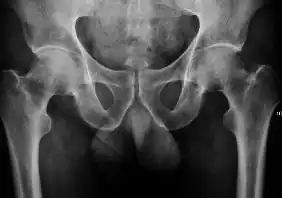

Projectional radiography ("X-ray") is the first imaging technique of choice in hip pain, not only in older people with suspected osteoarthritis but also in young people without any such suspicion. In this case plain radiography allows categorization as normal hip or dysplastic hip, or with impingement signs, pincer, cam, or a combination of both.[1]

X-Ray

Projectional radiography ("X-ray") is currently useful not only in older people in whom osteoarthritis of the hip is suspected but also in younger people without osteoarthritis, who are being evaluated for femoroacetabular impingement (FAI) or hip dysplasia.[1]

Plain radiography allows us to categorize the hip as normal or dysplastic or with impingement signs (pincer, cam, or a combination of both). Besides these, pathologic processes like osteoarthritis, inflammatory diseases, infection, or tumors can also be identified (Figure 1).[1]

X-ray in adults

- Hip dysplasia

Measurements of hip dysplasia in adults are quite different from those in children.[1]